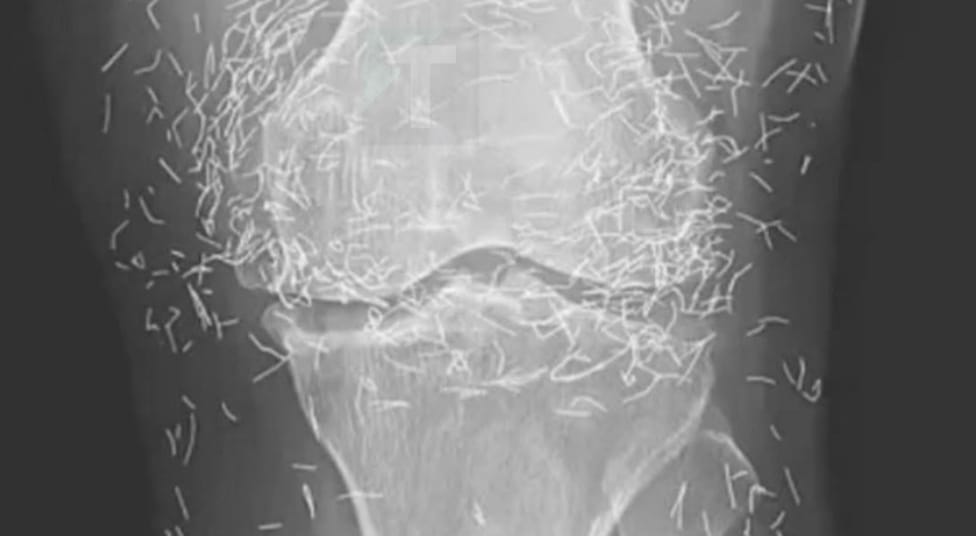

Καθώς οι γιατροί εξέταζαν μια ακτινογραφία από τα γόνατα μιας ηλικιωμένης γυναίκας που υπέφερε από έντονους πόνους στις αρθρώσεις, ανακάλυψαν έναν πραγματικό «θησαυρό»: εκατοντάδες μικροσκοπικές χρυσές βελόνες βελονισμού που είχαν μείνει μέσα στους ιστούς της.

Στην περίπτωση της γυναίκας, οι βελόνες, οι οποίες θεωρείται ότι ήταν φτιαγμένες από χρυσό, είχαν σκόπιμα αφεθεί μέσα στον ιστό για συνεχή διέγερση, όπως αναφέρει η έκθεση.

Επίσης, μπορεί να δυσκολέψουν την ανάγνωση μιας ακτινογραφίας. «Οι βελόνες μπορεί να κρύψουν κάποια ανατομικά στοιχεία», δήλωσε ο Guermazi.